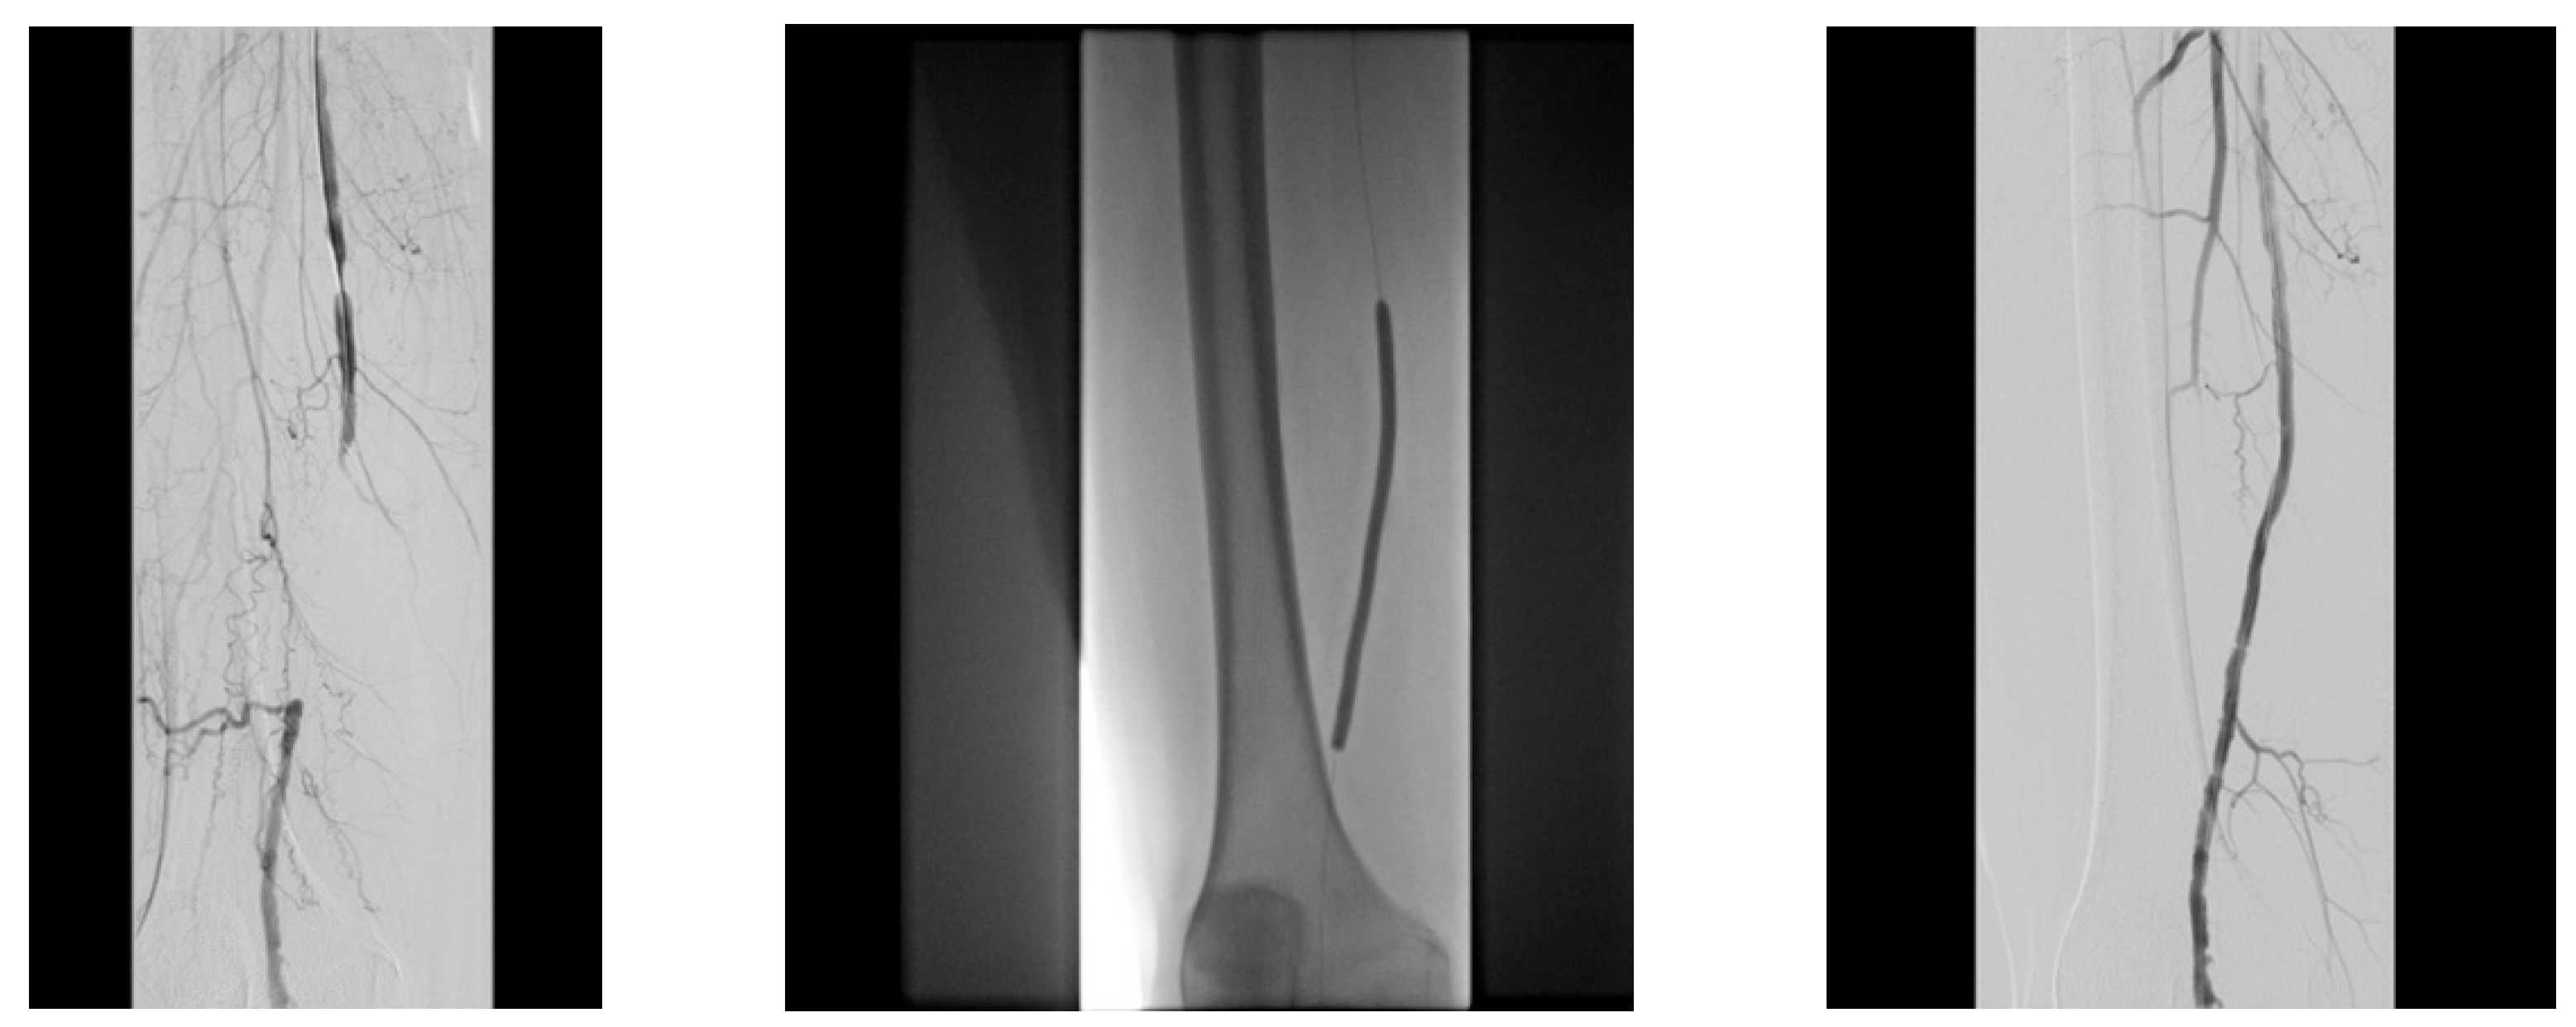

4.1. Case 1—Direct Revascularization-Minor Amputation

4.2. Case 2—Indirect Revascularization-Major Amputation